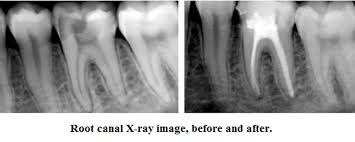

After the diseased pulp is removed, the pulp chamber and root canals are flushed and cleaned

Step 3 Filling the root canals

After cleaning and drying, it's time to fill the interior of the tooth the empty pulp chamber and root canals.